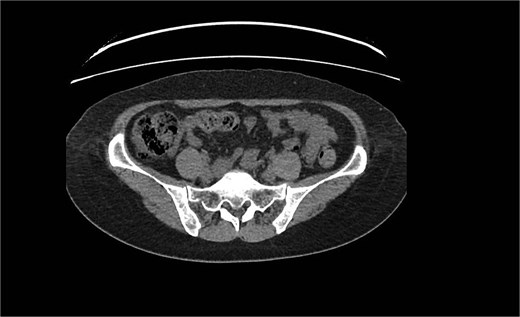

Unenhanced CT of the abdomen and pelvis using the standard kidney, ureter, and bladder concluded that a 5 × 6 × 3 mm stone was in the right renal pelvis with proximal mild back pressure; the appendix measured 12.5 mm, showing a thick wall and surrounding fat stranding, as seen in Fig. 1.

Dilated tubular structure with signs of fat stranding suggesting appendicitis.